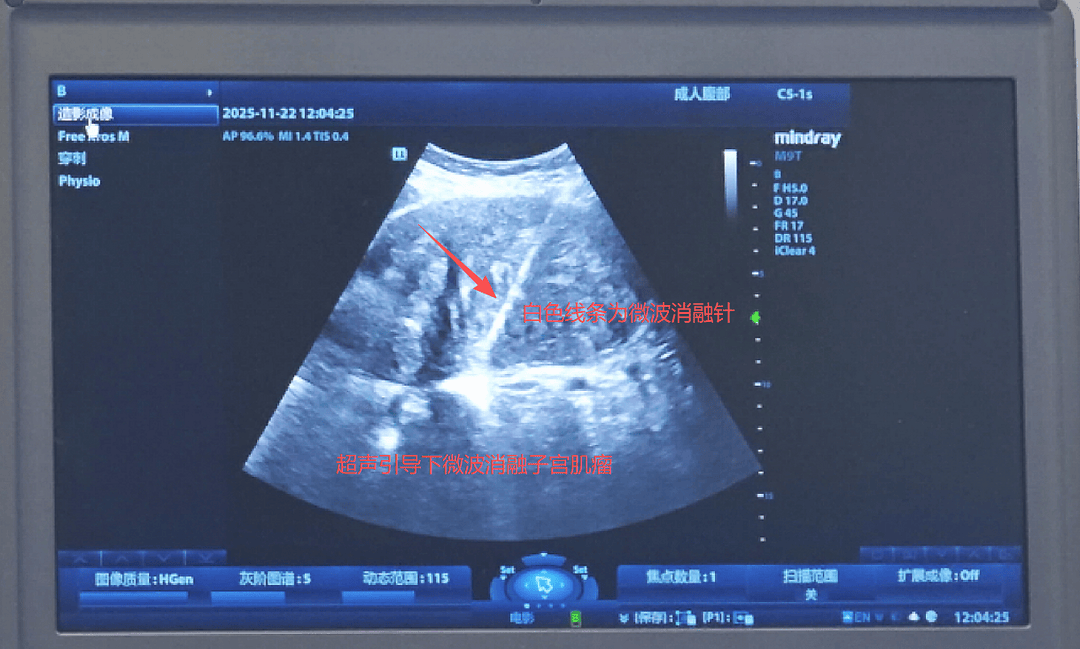

次日,曹主任带领团队为周女士实施了子宫肌瘤微波消融术。在全身麻醉下,仅一个多小时便顺利完成手术,术后当天周女士就能下床活动。